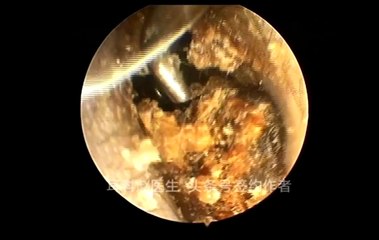

There are many home remedies to get rid of ear wax. This video offers useful information on earwax blockage plus some of the most effective treatments you can try at home.